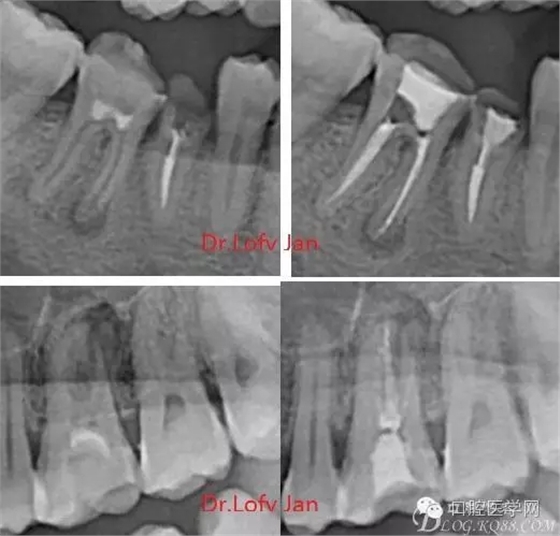

曲面斷層片在未試尖根管治療中的病例整理

前言:自己做的一些曲面斷層片在未試尖根管治療中的病例整理,發(fā)現(xiàn)問題很多包括自身的,技術(shù)的,還有設備的問題,予以總結(jié)整理并期待進一步提高。

①有助于發(fā)現(xiàn)牙體和根尖周組織的異常改變,如牙折、牙內(nèi)吸收、髓腔鈣化及根尖囊腫;

②有助于確定牙根和根管的數(shù)目、位置、形態(tài)、方向和彎曲情況;

根管治療術(shù)是牙體牙髓疾病治療中最復雜和最關(guān)鍵的治療項目。根管充填材料抵達根尖、并能嚴密堵塞根尖孔,是確保根管治療效果的關(guān)鍵指標。為了保證根管充填到位,醫(yī)生需要在術(shù)前照牙片以了解牙根根管的數(shù)量、彎曲程度和長度,在術(shù)中有時需要插針照牙片來精確測量根管長度,術(shù)后必須照牙片以確定是否根管充填到位,如果欠填或超填,就需要重新充填、重新照牙片確認,直到根管充填到位。所以,在患者接受根管治療時有時會反復照牙片。

病例分析:曲面斷層片在x線輔助診斷與檢查中目前大多數(shù)文獻和著作都建議只能作為初診拍片檢查手段,不能作為終末疾病的確診與手術(shù)療效的評價指標,臨床大部分中小型門診都因為設備不齊全導致信息偏差很大。